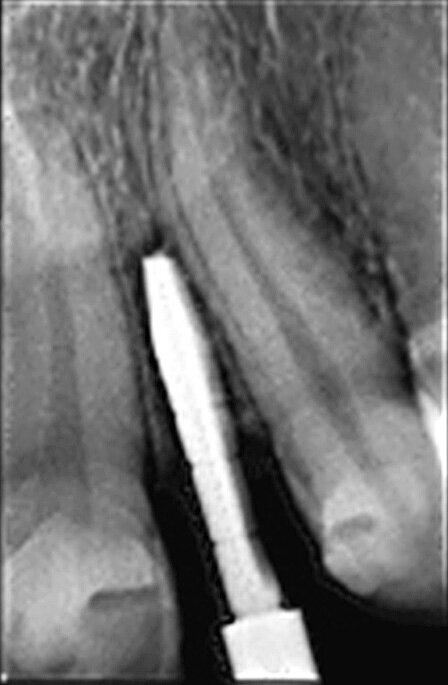

Une jeune femme de 21 ans, en bonne santé, nous a consultés pour un problème d’agénésie de l’incisive latérale gauche maxillaire. Elle avait suivi un traitement orthodontique durant trois ans au bout duquel l’orthodontiste n’avait pu obtenir qu’un espace mésio-distal de 4 mm entre le point de contact mésial de la canine supérieure gauche et le point de contact distal de l’incisive centrale gauche maxillaire. L’analyse de la radiographie périapicale numérique a montré qu’au-delà des six premiers millimètres sous le niveau de l’os crestal, 2,7 mm seulement séparaient les racines des deux dents, et après 8 mm, la distance n’était plus que de 2,1 mm (Fig. 2). Nous avons conseillé un second traitement orthodontique à la patiente, mais elle a refusé et nous avons donc discuté de la pose d’un implant étroit par la technique d’ouverture de l’espace inter-radiculaire. L’implant avait un diamètre de 3 mm, une longueur de suivantes : implant Press-Fit inséré dans l’ostéotomie ; design en plateau sans filetage ; épaulement incliné assurant un diamètre inférieur au niveau du col (selon le concept dit du « platform-switching ») ; positionnement sous-crestal à 1–3 mm sous le niveau de l’os crestal. La patiente a été anesthésiée par une injection d’articaïne et d’épinéphrine (Septocaïne, Septodont), et une légère incision crestale au moyen d’une lame de bistouri de 15c a été réalisée. Le foret-guide a été utilisé à une vitesse de rotation de 1 100 tr/min afin de perforer l’os cortical jusqu’à une profondeur approximative de 4 mm. Un alésoir manuel de Ø 2,5 mm puis un second de Ø 3 mm ont été utilisés pour effectuer pour ouvrir l’espace entre les racines.3, 4

Fig. 2 : Radiographie périapicale du site de l’agénésie de l’incisive latérale gauche maxillaire. L’espace entre les racines des dents 21 et 23 est toujours problématique après le traitement orthodontique.